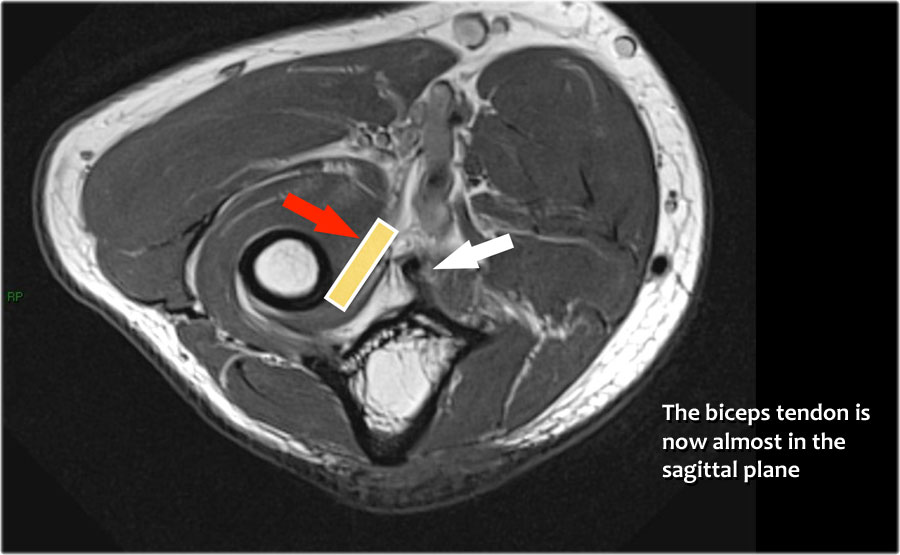

Cuộn qua các hình ảnh cắt ngang của gân cơ nhị đầu từ chỗ nối cơ-gân đến điểm bám tận trên lồi củ xương quay.

Bệnh lý của gân cơ nhị đầu đoạn xa rất giống với bệnh lý của gân Achilles.

Có thể gặp thoái hóa gân, rách một phần và rách hoàn toàn có hoặc không có sự co rút.